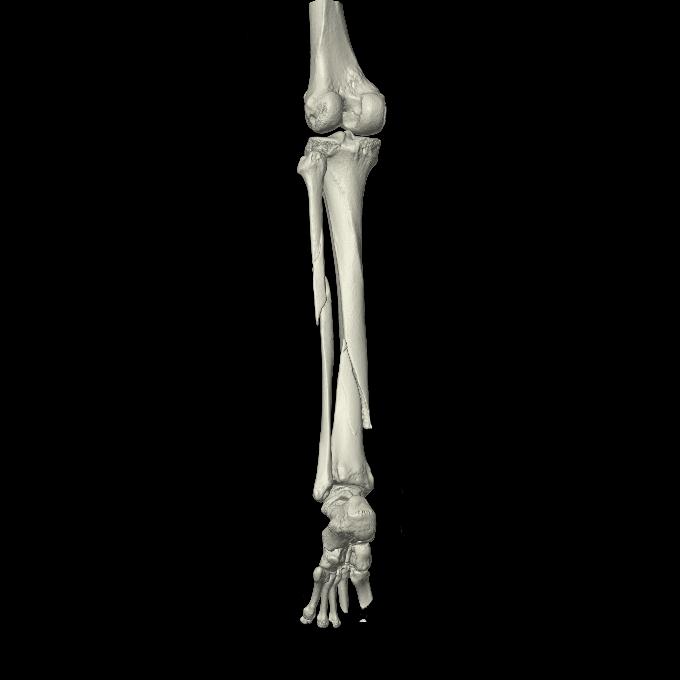

102803 1/12(キウスなし) 1/27 左下腿 4R 30歳女性 左脛骨軸内釘

102755 1/4 2R 1/15 2R 右足関節 68歳女性 右三果脱臼骨折